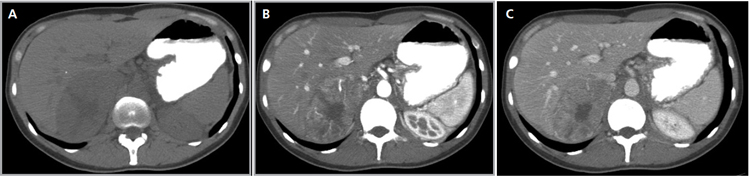

En la TC no contrastada las glándulas suprarrenales normales son homogéneas y simétricas, con una densidad muy similar a la del parénquima renal adyacente (Figura 1 a). Con un medio de contraste ev la glándula suprarrenal se opacifica en forma homogénea, similar al hígado o al bazo (Figura 1 b). Si la cantidad de tejido adiposo retroperitoneal es abundante las glándulas suprarrenales pueden aparecer enteramente rodeadas por grasa y su delimitación es más fácil (Figura 2 a); lo inverso ocurre en pacientes muy delgados con escasa grasa retroperitoneal (Figura 2 b). En RM, en secuencias ponderadas en T1 y T2 convencionales tienen una intensidad de señal homogénea, hipointensa respecto de la grasa adyacente e iso o hipointensa con respecto del parénquima hepático (Figura 3 a y b). En los cortes coronales se aprecia mejor la forma y la posición de las glándulas suprarrenales (Figura 3 c).

Figura 1. Glándula suprarrenal normal en tomografía computada. Cortes axiales de tomografía computada, donde se identifica la morfología normal de la glándula suprarrenal derecha (flecha) en fase no contrastada (a), y tras el uso de medio de contraste endovenoso (b).